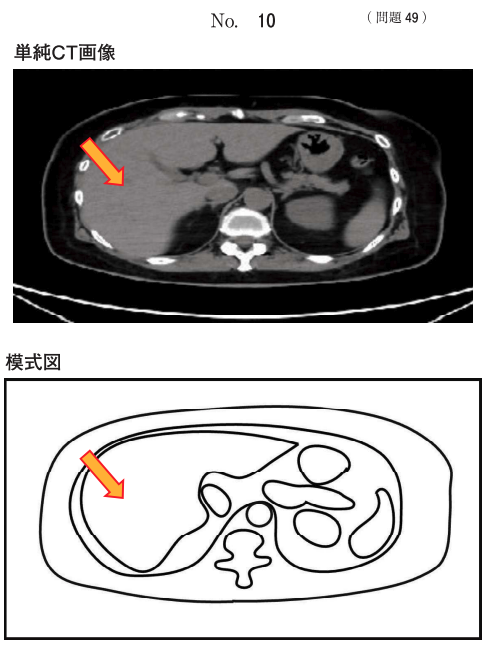

71回 午前 問題49

肝前性黄疸の原因はどれか。

2

【この問題のポイント】

この問題は、黄疸を発生部位(肝前性・肝性・肝後性)で分類し、それぞれの代表的原因疾患を対応づけられるかを問う問題。

肝前性黄疸は肝臓に到達する前の段階でビリルビン産生が過剰になる状態で、主に溶血などで非抱合型(間接)ビリルビンが増加する。

一方、肝性黄疸は肝細胞障害や胆汁排泄障害、肝後性黄疸は胆道閉塞が原因で、抱合型(直接)ビリルビンが増加する。

2 溶血性貧血

赤血球破壊(溶血)が亢進し、ヘム代謝由来のビリルビン産生が過剰になる。

肝臓の処理能力を超えると非抱合型ビリルビンが増加し、肝前性黄疸の典型的原因となる。

尿中ビリルビンは陰性になりやすく、尿中ウロビリノーゲンは増加しやすい。